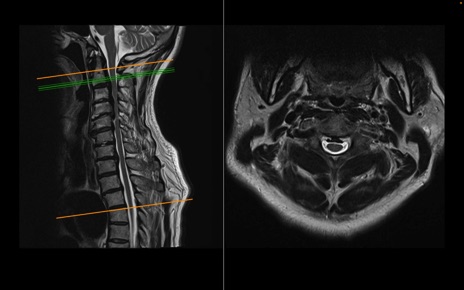

頚椎MRI

T1WI(矢状断像)

T2WI(矢状断像)